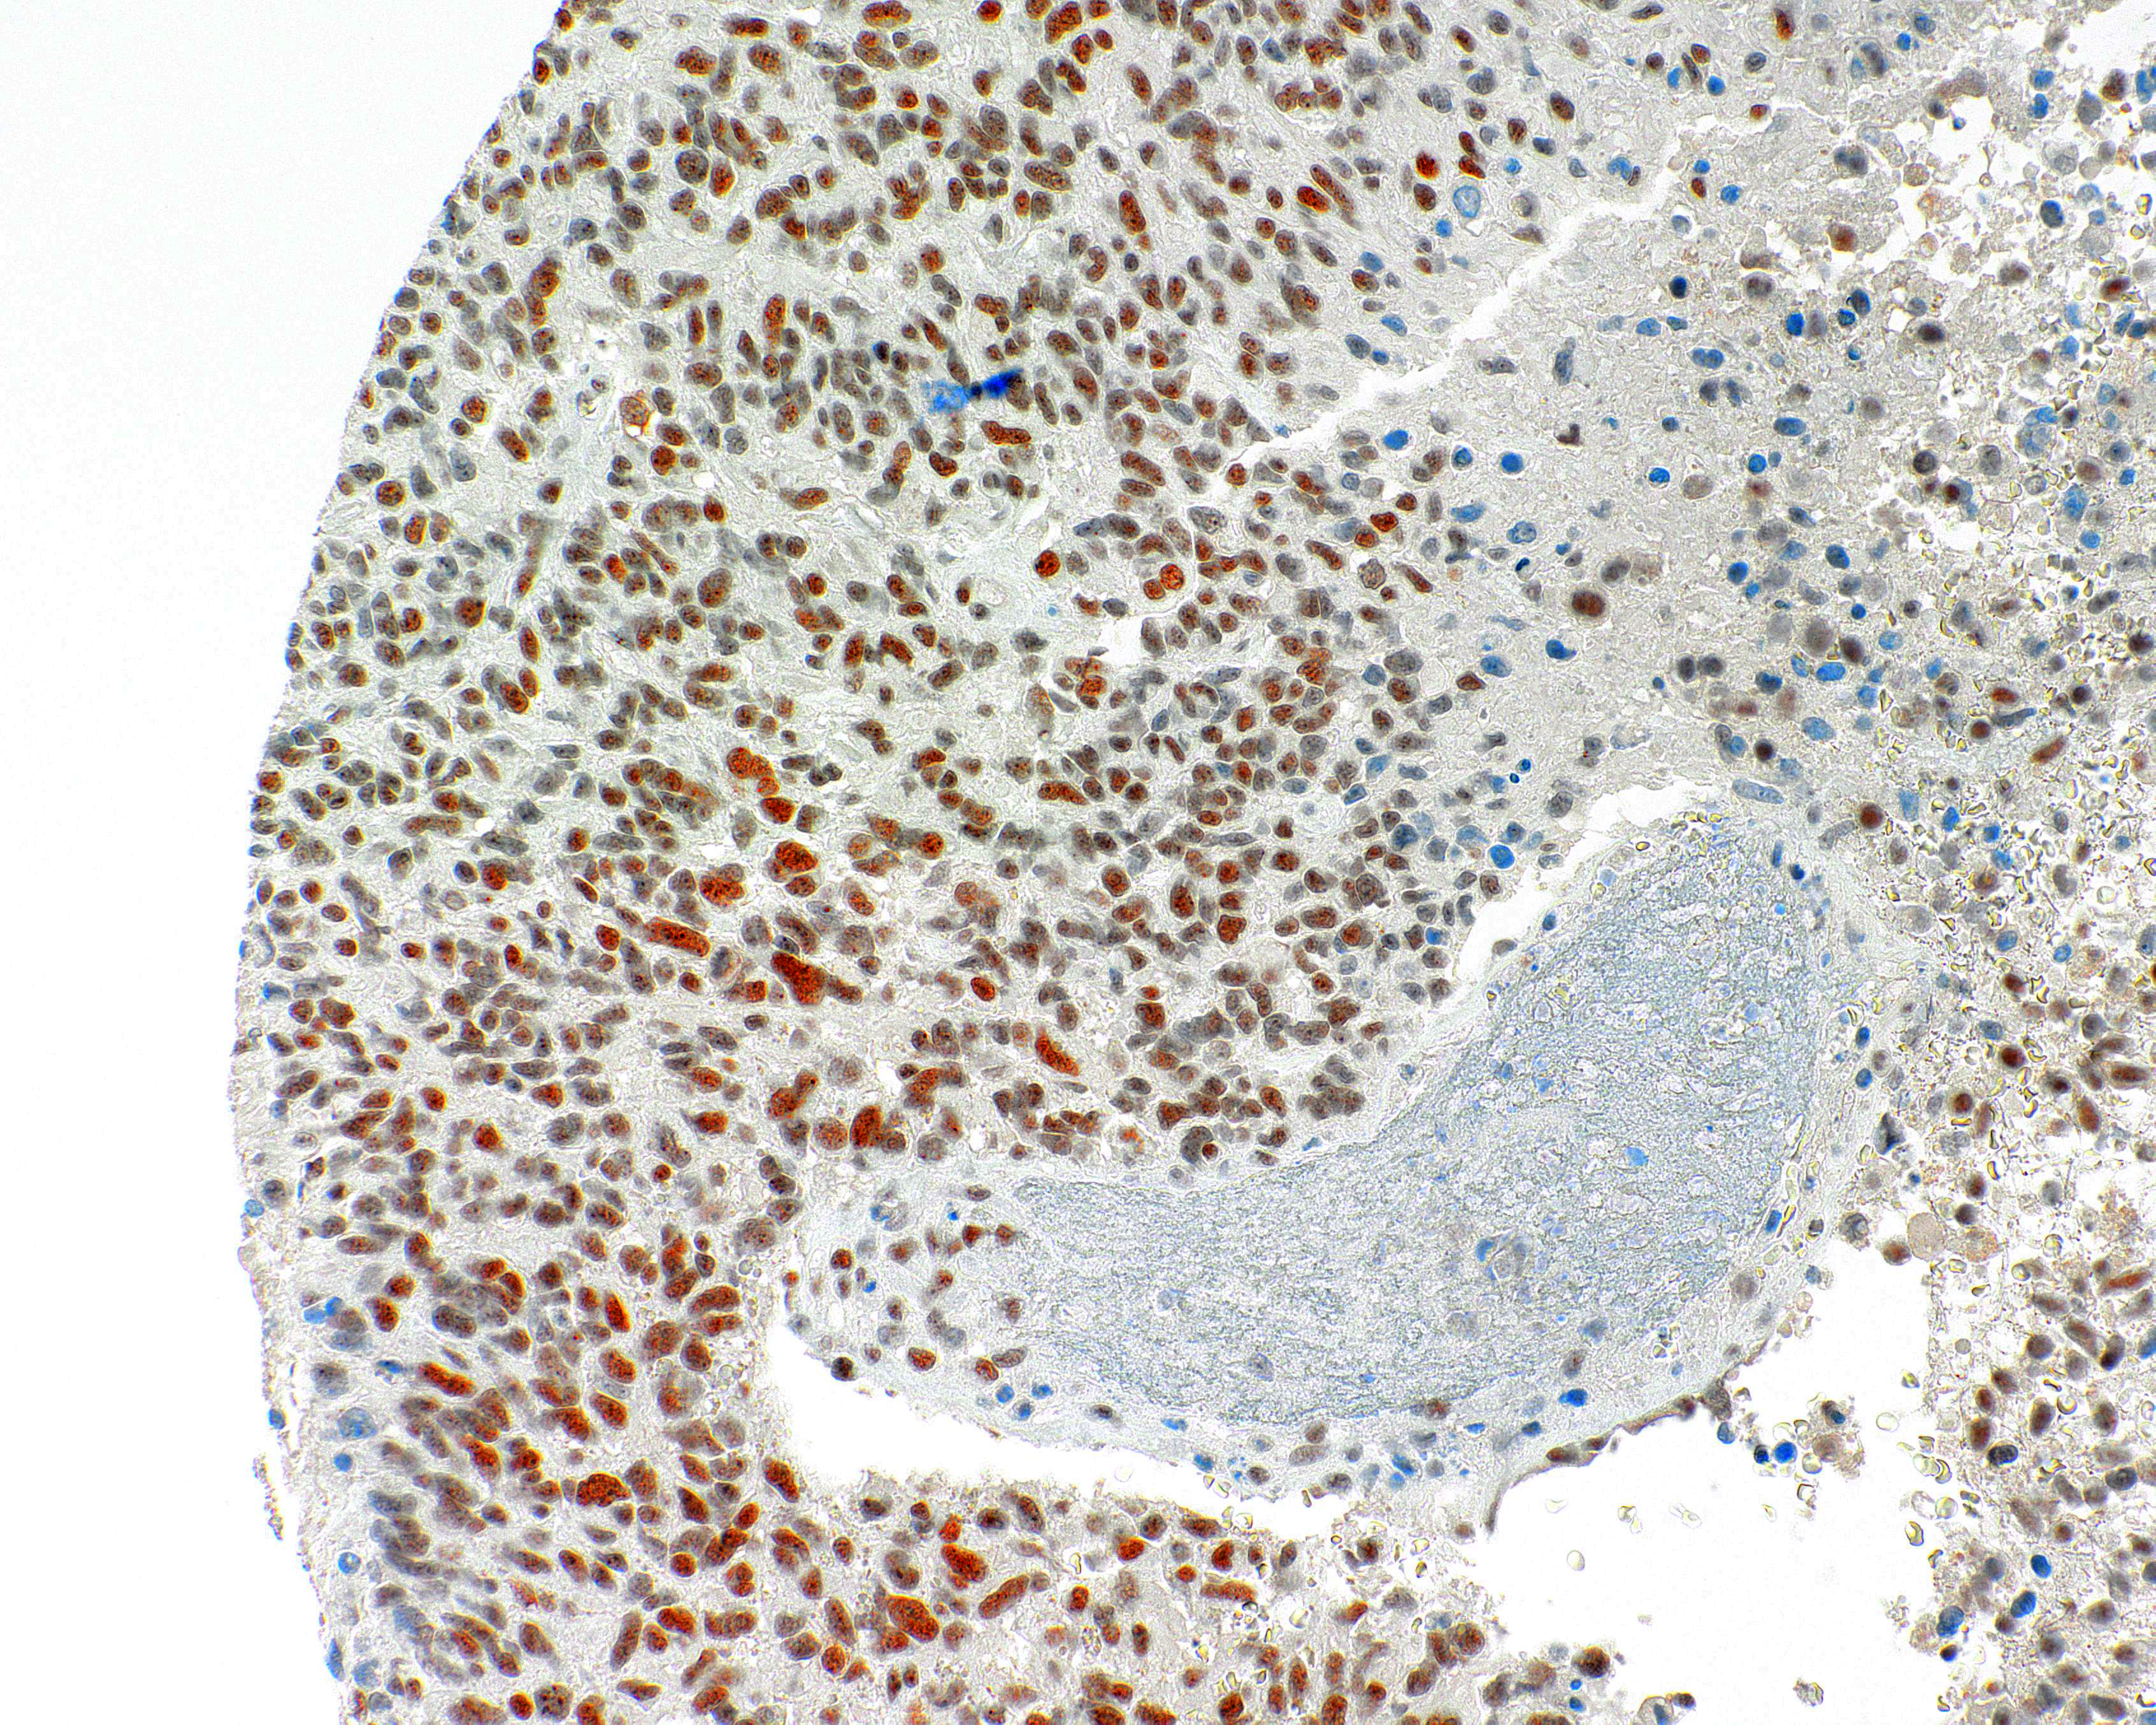

[Genomeme] ATRX

CLONE:

IHC703

HOST SPECIES:

Mouse

CLONALITY:

Monoclonal

POSITIVE CONTROL:

Glioma

INTENDED USE/REG. STATUS:

RUO

ATRX is involved in the remodeling of the nucelosome structure, and facilitate the transcription and replication. ATRX loss occurs in grades II/III astrocytomas and glioblastomas and comes together with IDH1 mutations. Detection of ATRX with IHC acts a sensitive method to identify the mutations.